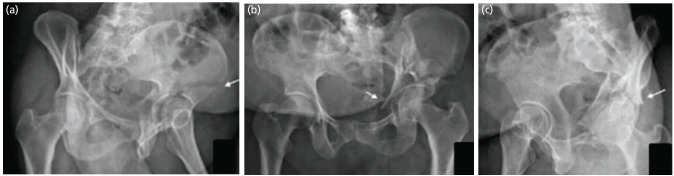

Introduction: We have devised an algorithm to assist classifying acetabulum fractures using plain radiographs. This study aimed to test if the accuracy and reliability of fracture classification increases using our algorithm in resident doctors.

Materials and methods: Seventy-two residents of eight tertiary care institutes took part in our survey. These residents were divided into three groups, Groups A, B, and C, with 31, 20, and 21 residents, respectively. Two different Collections (1 and 2) containing radiographs of twenty patients each, with known classification from CT and intra-operative findings, were prepared. Collection 1 radiographs were given to Group A and B, and Collection 2 radiographs were given to Group C. Group A residents were asked to classify the fractures using our algorithm, and Group B and C residents were asked to classify the fractures according to their understanding. Intra-observer and interobserver reliability were estimated.